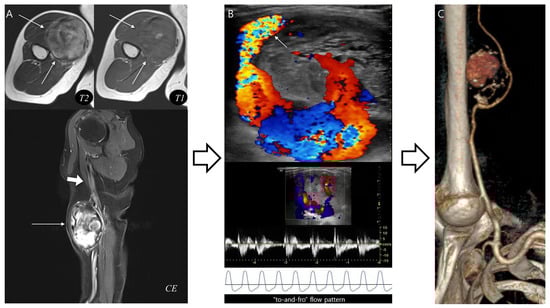

Using the proposed diagnostic flowchart, we successfully applied this approach in representative cases. In a representative pseudoaneurysm case (Figure 3), the hematoma-like lesion demonstrated a central flow void with adjacent neurovascular bundle involvement on MRI, which allowed a confident diagnosis of pseudoaneurysm; the patient subsequently underwent successful endovascular embolization. In contrast, in a CEH case (Figure 4), the lesion exhibited a multilobular hematoma-like lesion with internal septations and lacked neurovascular bundle involvement, findings that favored the diagnosis of CEH and were later confirmed after wide surgical excision. These representative cases underscore the practical utility of the flowchart by illustrating how specific imaging features can be translated into accurate diagnostic decisions and directly guide appropriate therapeutic strategies.

Figure 3.

Diagnosis and treatment of pseudoaneurysm. (A) Axial T2-weighted, T1-weighted, and coronal T1-weighted contrast-enhanced MR images show an intramuscular, ovoid lesions (arrow) in the upper arm. The lesion demonstrates a central flow void with inner peripheral high SI on T1-weighted image (arrow, mural thrombus) with neurovascular involvement (arrowhead). (B) Digital subtraction angiography reveals a pseudoaneurysm sac (arrow) with a narrow neck arising from the brachial artery (arrowhead). (C) Post-embolization angiography demonstrates successful occlusion of the pseudoaneurysm neck (arrowhead).

In the last pseudoaneurysm case (Figure 5), typical MRI findings, such as a central flow void was equivocal and inner peripheral high SI on T1WI was absent, making the diagnosis more challenging. Instead, the presence of neurovascular bundle involvement raised strong suspicion for pseudoaneurysm which was subsequently confirmed by complementary vascular imaging. This case demonstrates that the diagnostic flowchart retains its clinical value even in atypical presentations, underscoring the importance of integrating ancillary features such as neurovascular involvement to achieve accurate diagnosis and ensure appropriate treatment.

Figure 5.

Pseudoaneurysm with neurovascular bundle involvement diagnosed without biopsy. (A) Axial T2-weighted and T1-weighted MR images demonstrate a hematoma-like lesions (thin arrows) with equivocal central flow void or absent inner peripheral high SI. However, neurovascular bundle involvement (thick arrow) in sagittal T1-weighted contrast-enhanced MR image raises suspicion for pseudoaneurysm. (B) Doppler ultrasonography reveals a characteristic “Yin-yang” sign with neck at the brachial artery (arrow), confirming a “to-and-fro” flow pattern. (C) CT angiography with 3D reconstruction demonstrates a pseudoaneurysm arising from the brachial artery, consistent with the MRI suspicion. This case highlights that recognition of distinct MRI features can guide appropriate diagnosis without unnecessary biopsy.